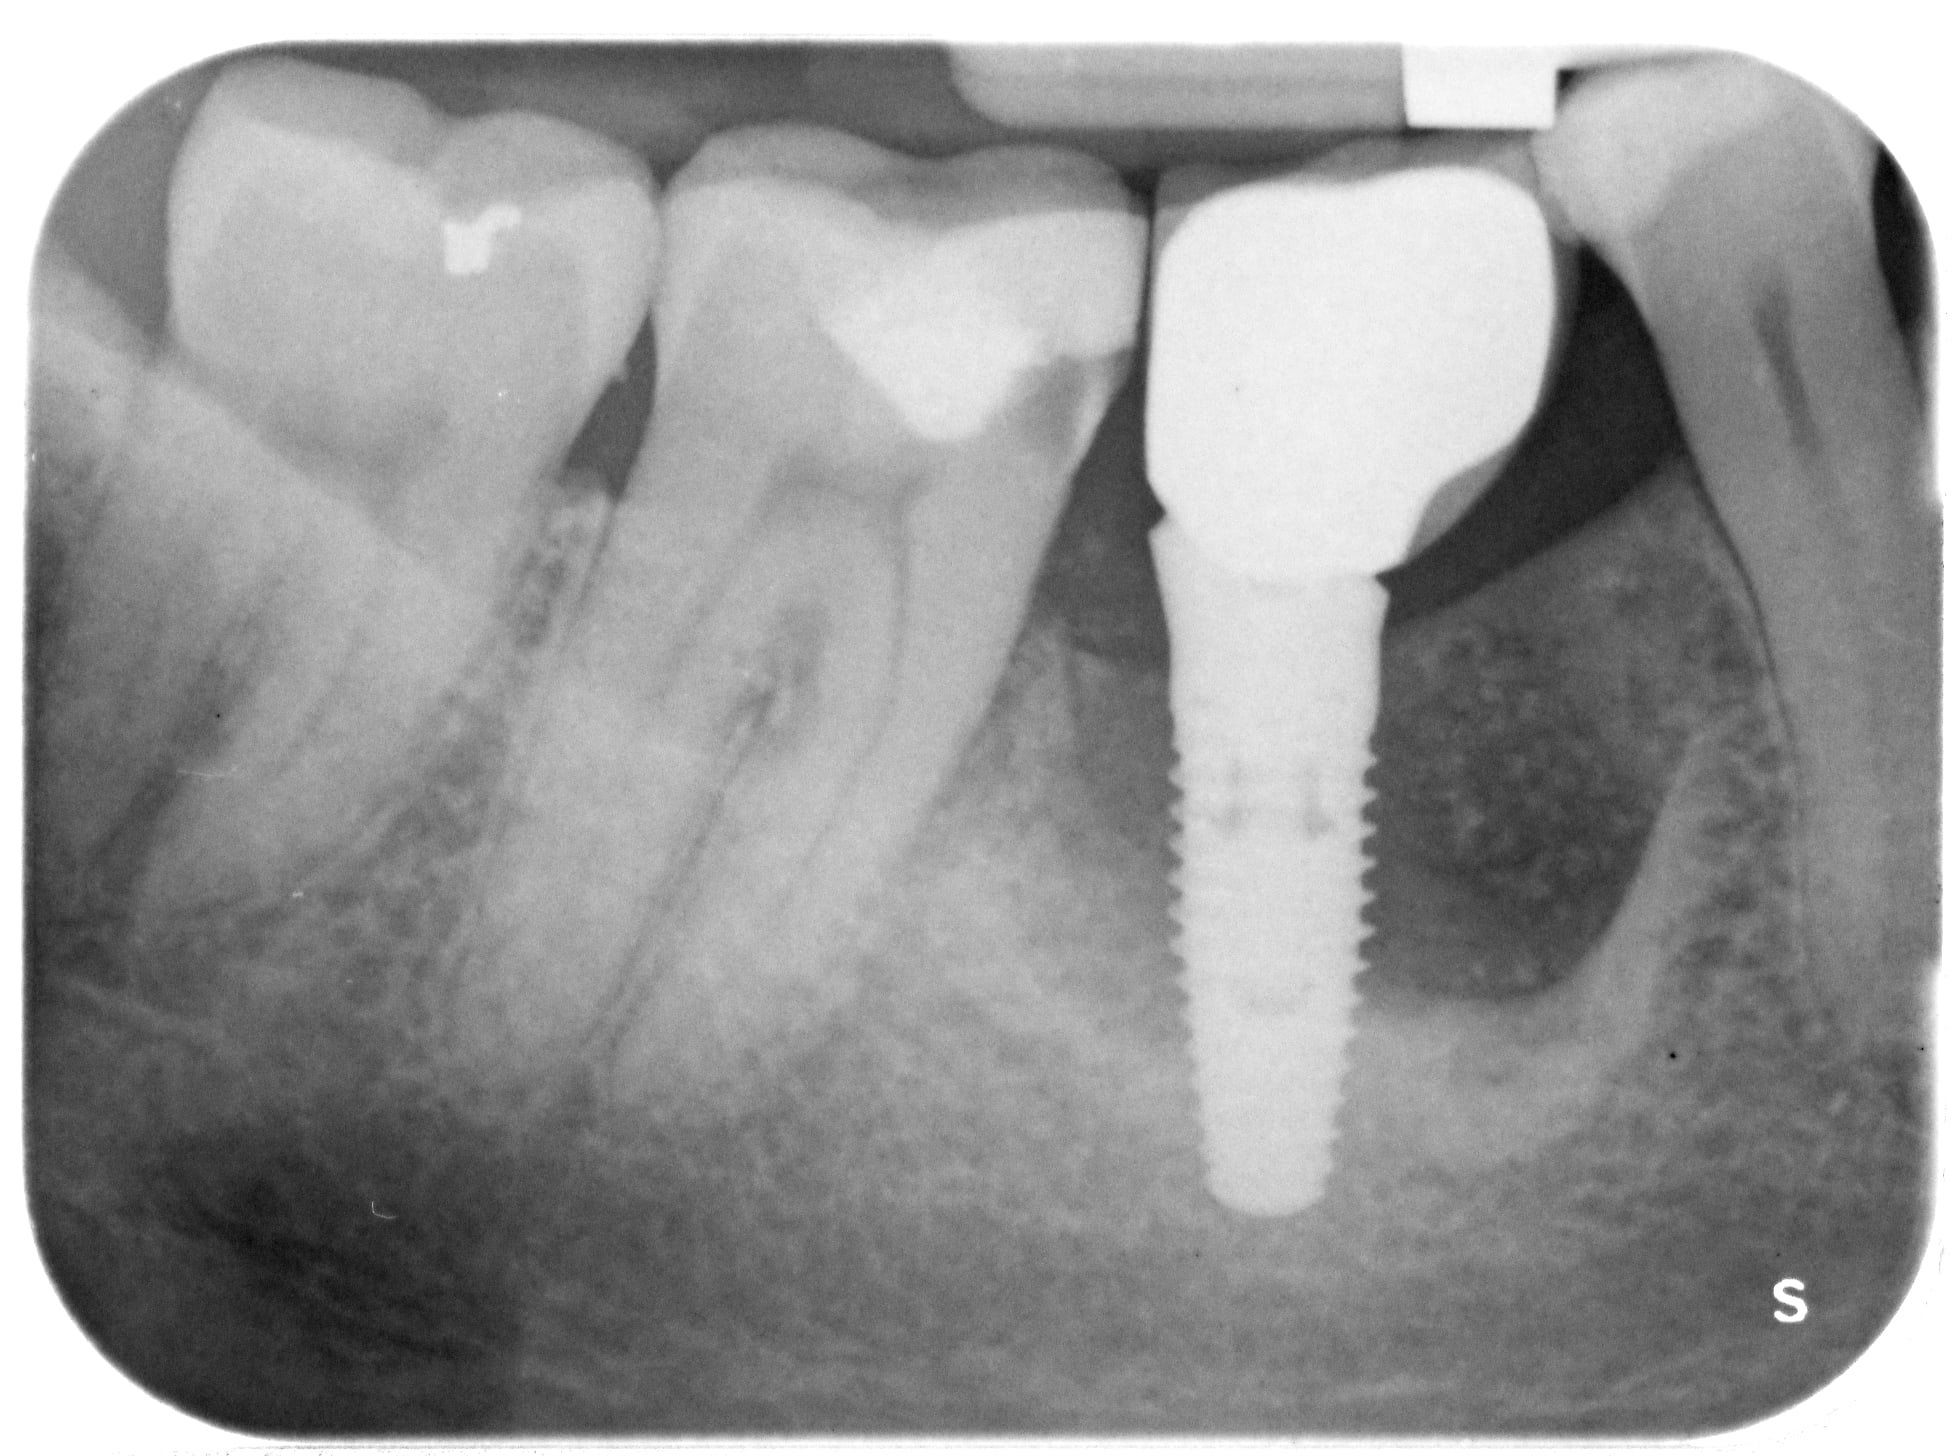

Je dois déposer ce joli clou, posé il y a 8 ans par un confrère, mais qui n' pas gardé les références des implants posés avant son changement de logiciel (il y a 5 ans).

Je pense que c'est du Nobel Replace, mais n'en suis pas sur...?

Ça ressemble en effet à du replace

Nan, pour commander le bon tourne-à-gauche chez Nobel (je connais pas du tout leur gamme). Contrairement à ce que laisserai penser la radio il tient bien, et comme il a été posé au contact du NAI et je veux pas y aller à la fraise ou à la trépine.